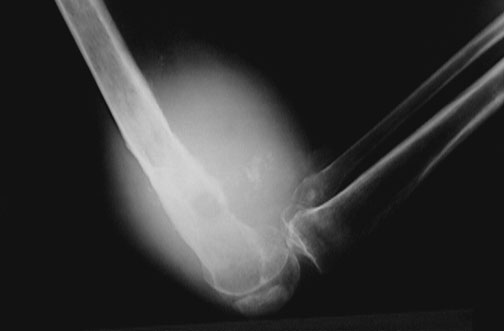

The distal femur has a mass lesion that is producing bony destruction as it involves the soft tissues of the lower thigh above the knee. This is a fibrosarcoma.